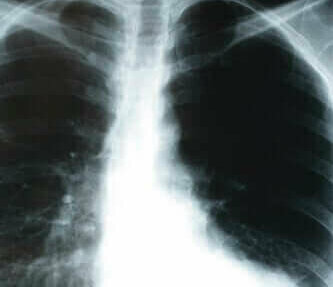

Ze bleken echter toch symptomen van Covid-19 te hebben toen de arts besloot het zuurstofgehalte in hun bloed te meten of een thoraxfoto te laten maken.

Als de arts dus vermoedt dat iemand het coronavirus heeft opgelopen, dan wordt aangeraden om de zuurstofverzadigingsniveaus te meten en een thoraxfoto maken. Dit is vooral belangrijk als iemand contact met iemand heeft gehad die besmet is of in het geval van mensen met een verhoogd risico.